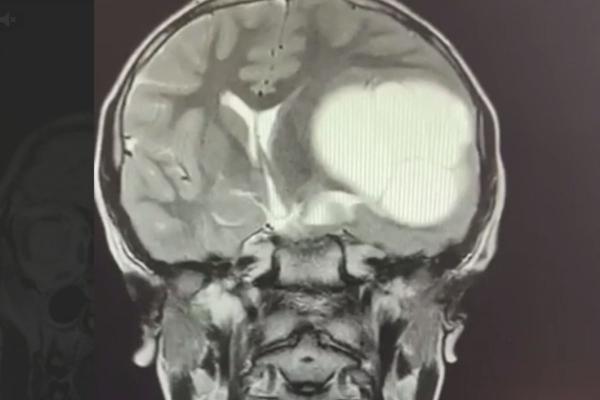

Челябинские медики извлекли из мозга школьника 12-сантиметровый «клубок» ленточных червей. Причиной редкого заболевания скорее всего стали немытые руки, сообщает телеграм-канал Baza.

Сначала 12-летний Миша стал хуже учиться и жаловался на головную боль. Когда школьник стал неразборчиво писать и захромал, родители обратились в больницу. Там ребенку провели МРТ и диагностировали редкое заболевание – эхинококкоз головного мозга. Личинки червей проникают в мозг через кровоток, а заражение, как правило, происходит через грязные руки.

Мальчику провели сложную операцию в Челябинской детской областной клинической больнице и удалили образование в мозге. Сейчас ребенок восстанавливается, у него прошли головные боли и почти вернулась нормальная координация.